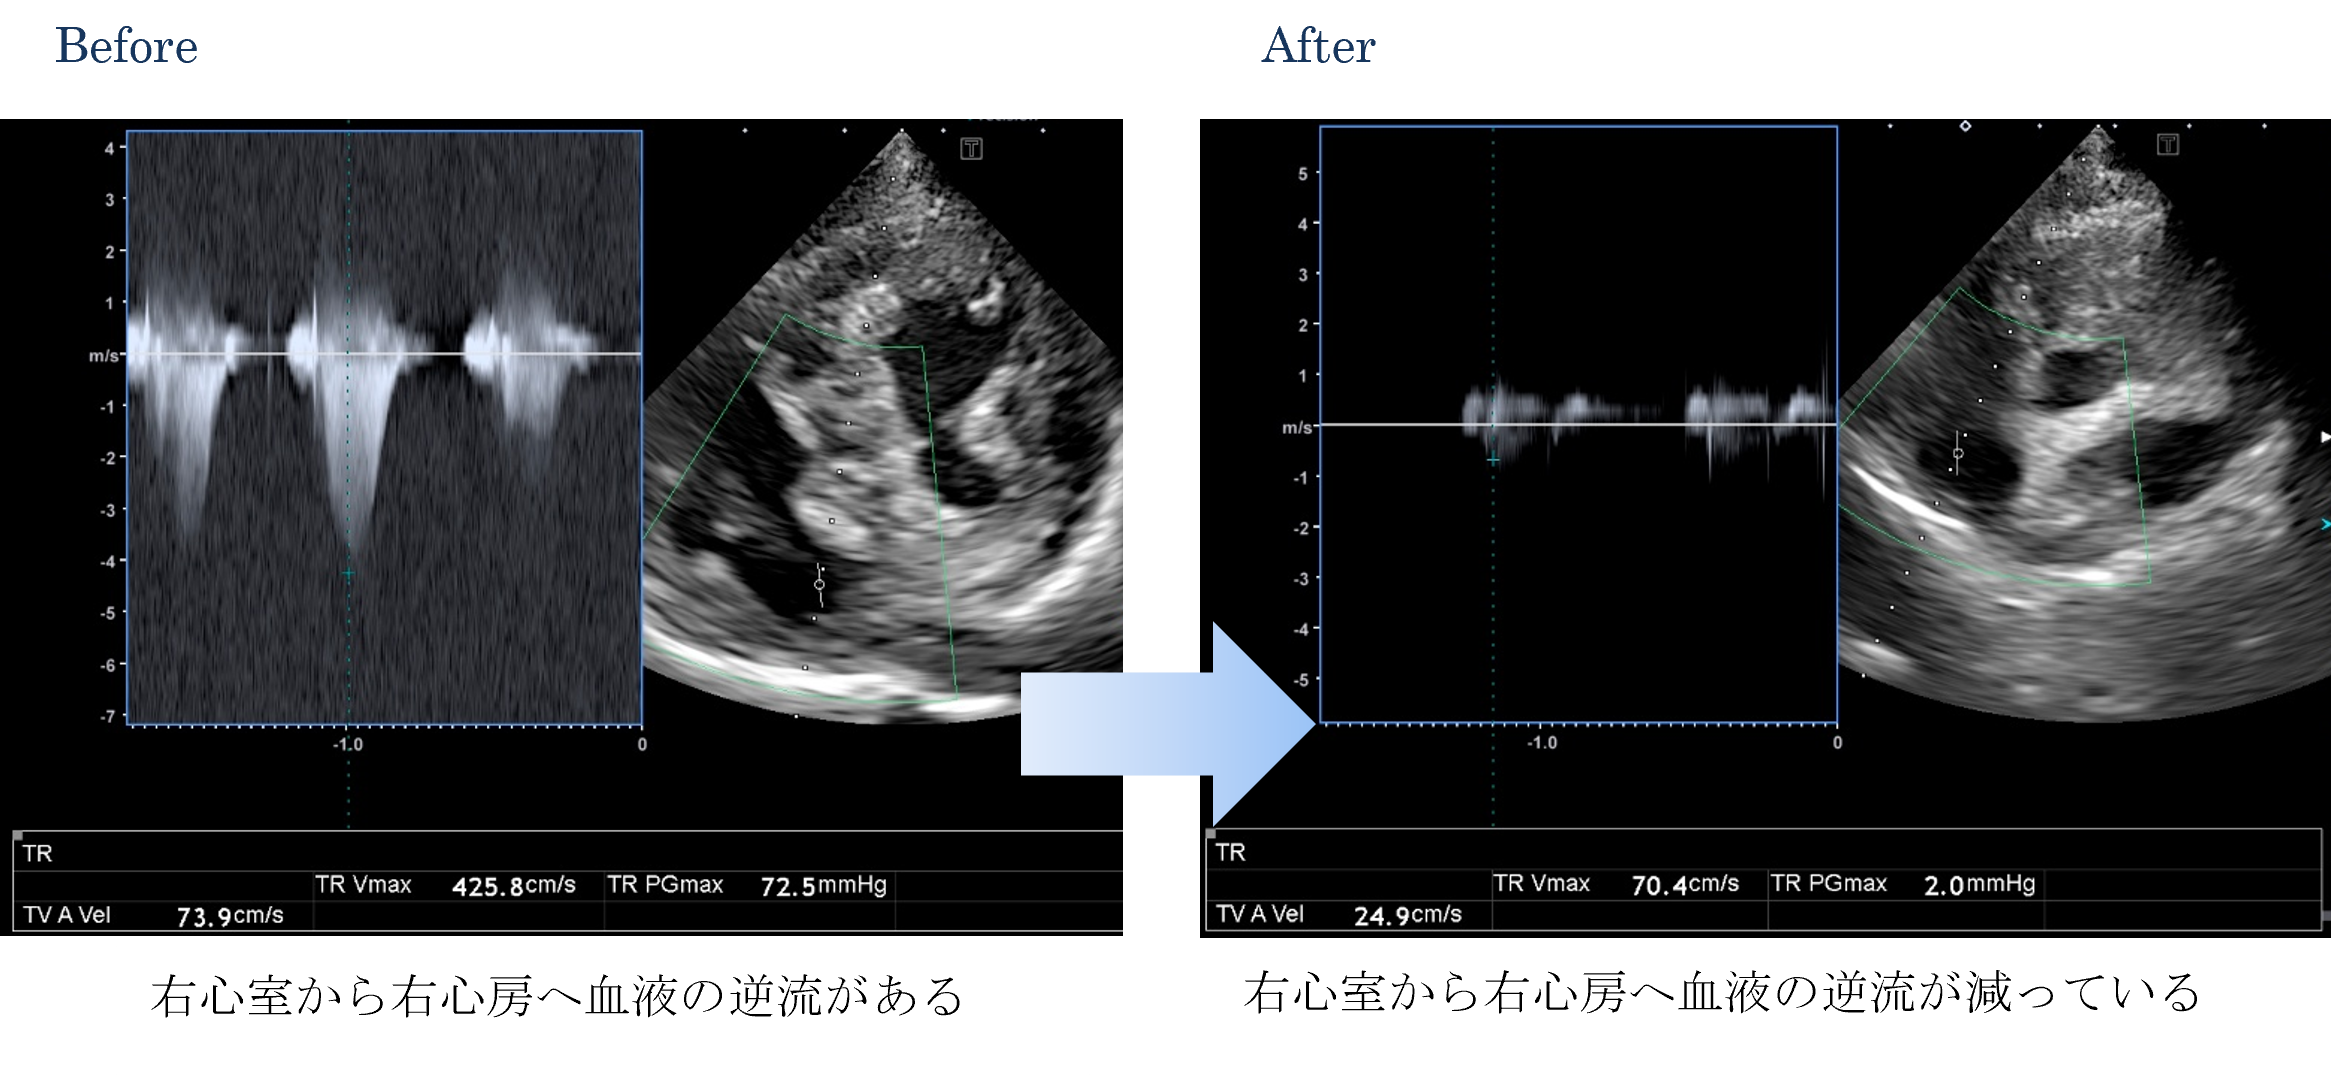

各種検査より、肺高血圧症と診断しました。

ご家族と相談した結果、ICUに入院して内科的治療(薬による治療)を行いました。

退院後は内服薬を継続してもらい元気に過ごすことができました。